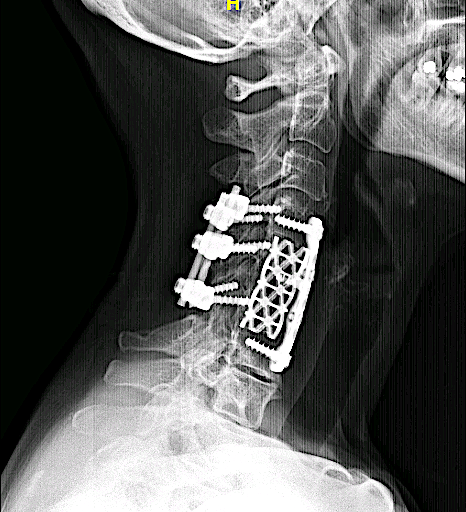

Artrodesis cervical de más de 15 años de evolución en otro centro.

Dolor cervical alto con irradiación C3 refractario a tto médico